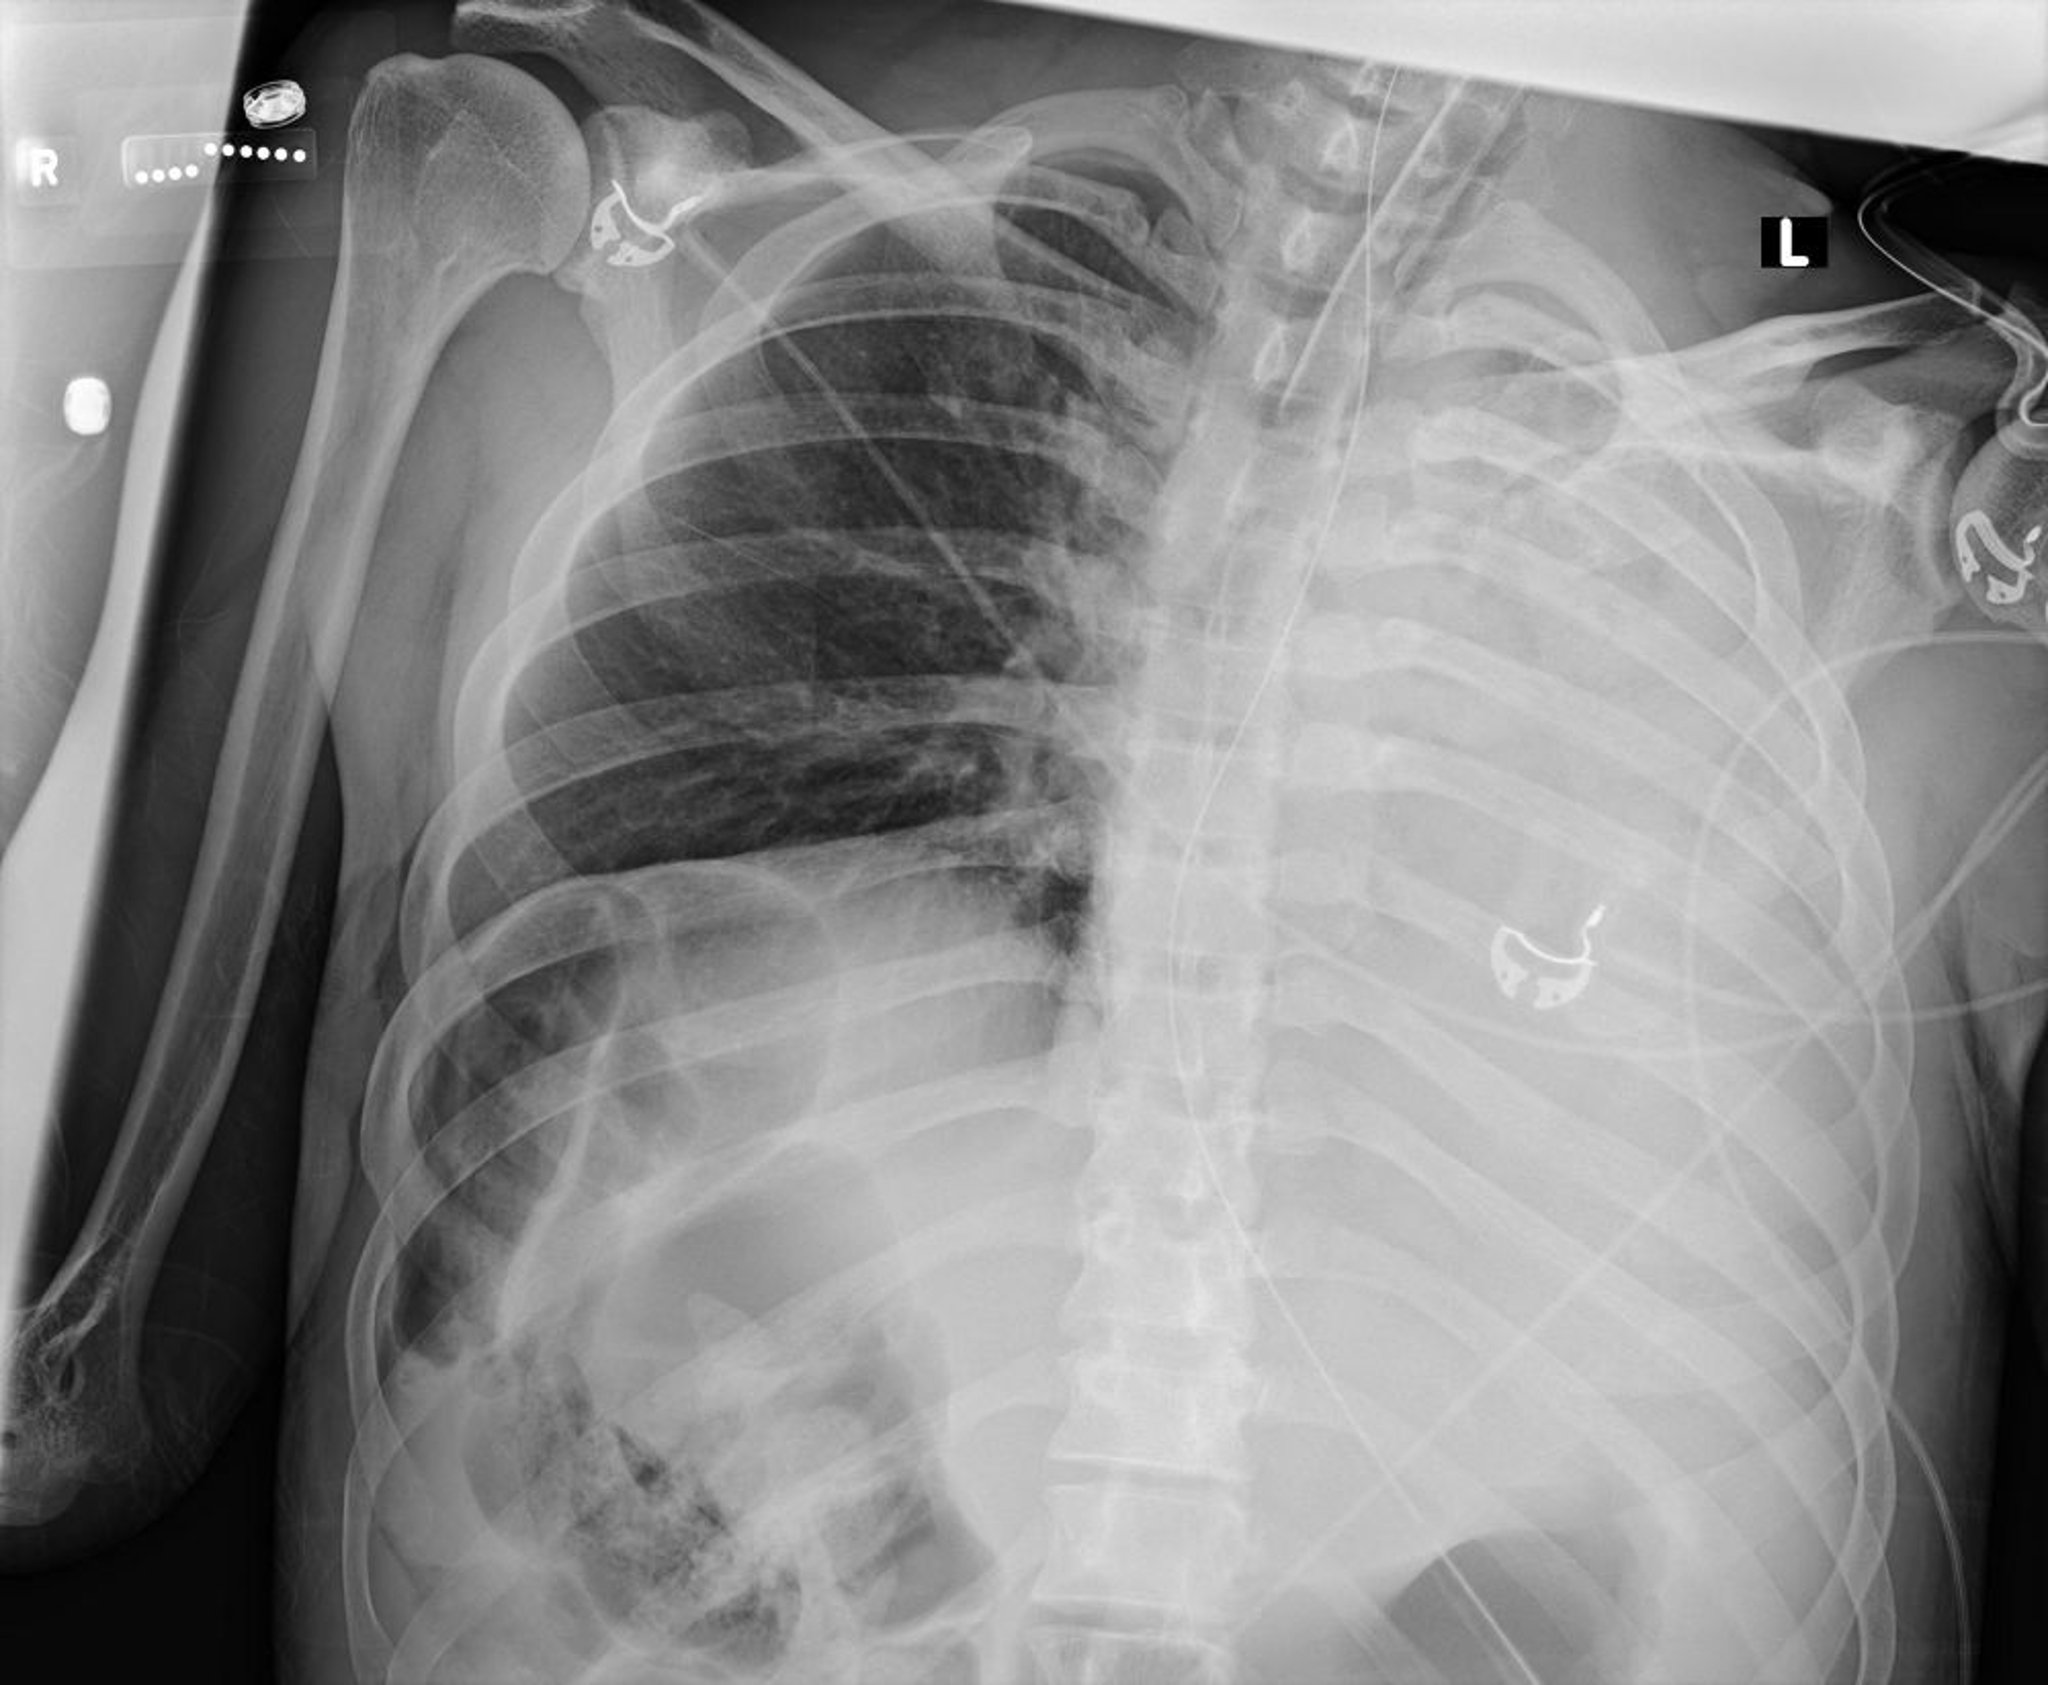

Atelectasis and Left Lung Collapse (Radiograph)

This chest radiograph shows collapse of all lobes of the left lung due to a mucus plug.

Courtesy of Alexander S. Niven, MD